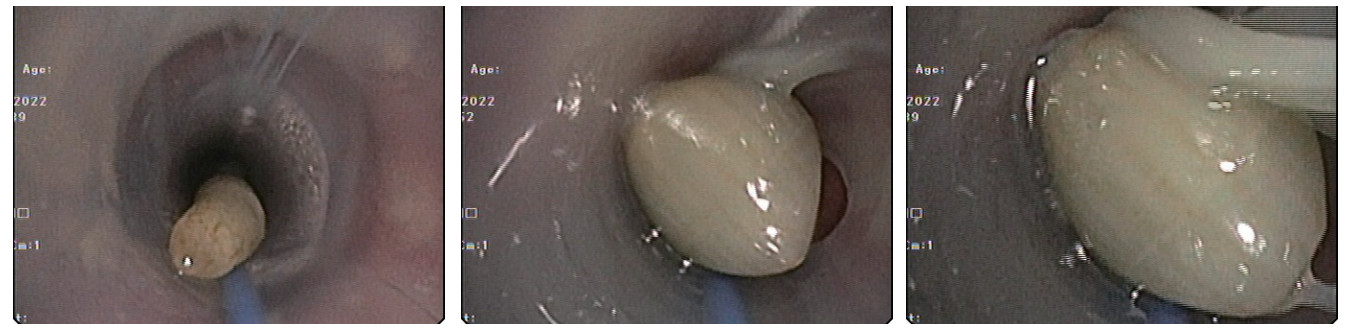

患者有明确高温暴露史,根据患者病史,查体及相关辅助检查,诊断“经典型热射病、Ⅰ型呼吸衰竭、支气管扩张伴感染、急性肾损伤”,继续予气管插管,呼吸机辅助呼吸,并每日监测气管插管气囊压力,迅速物理降温,抗感染,抗凝,补液扩容改善循环等对症治疗,经积极治疗后患者呼吸,循环等各项生命体征趋于稳定。患者白细胞明显高于正常值,且淋巴细胞占比明显增高,行骨髓穿刺活检后血液科专科会诊,诊断为“慢性淋巴细胞白血病,骨髓增殖性疾病”。患者住院2 d后开始出现阵发性呼吸困难,发作时伴大汗淋漓,夜间尤为明显,持续数分钟到数十分钟不等,症状发作时经皮血氧饱和度下降至90%,潮气量由约400 mL下降至约300 mL,两肺听诊可闻及少许哮鸣音,患者既往有慢性支气管炎病史,考虑支气管哮喘发作引起气道痉挛,应用甲基强的松龙针40 mg静脉注射,调整呼吸机参数,后患者呼吸急促逐渐缓解。入院第3天复查胸部CT(见图 2):“两肺感染性病变,右肺中叶、左肺上叶部分支扩伴感染,两侧胸腔少量积液伴邻近两肺下叶膨胀不全,气管及左侧支气管内条状高密度影”。根据胸部CT结果,气管及左侧支气管内高密度影考虑气道内痰液阻塞,加强翻身拍背,吸痰等对症治疗。入院第4天凌晨,患者再次出现呼吸急促,大汗淋漓,两肺听诊可闻及少许哮鸣音,经皮血氧饱和度下降至83%,潮气量明显下降至200 mL左右,血气分析提示:“PaO2:48 mmHg,PaCO2:30.5 mmHg,SatO2:83%,BE:-5 mmol/L,AB:18.5 mmol/L”。继续糖皮质激素应用缓解气道痉挛,鼓肺吸痰,上调呼吸机参数等综合治疗,0.5 h后患者氧合无明显改善,不排除气道梗阻可能,立即行床边纤维支气管镜检查,镜下见气管及左主支气管内有2条奶油色活动性虫体,给予夹出,夹出虫体后患者呼吸逐渐平稳,氧合明显改善(支气管镜下虫体图片详见图 3)。2条虫体为活虫,放置在生理盐水中可见活动,测量虫体长度约25 cm,虫体直径约5 mm(虫体全图详见图 4),经本院感染科及市疾控中心会诊后认定2条虫体为蛔虫成虫,故此,患者诊断“蛔虫病”明确,治疗上予阿苯达唑片400 mg/d鼻饲, 连续服用2日,驱虫治疗后5 d内大便中总共排出蛔虫成虫12条,驱虫治疗效果显著,病情好转。

| 图 3 纤维支气管镜下见蛔虫虫体 |

| 图 4 蛔虫虫体实物照片 |